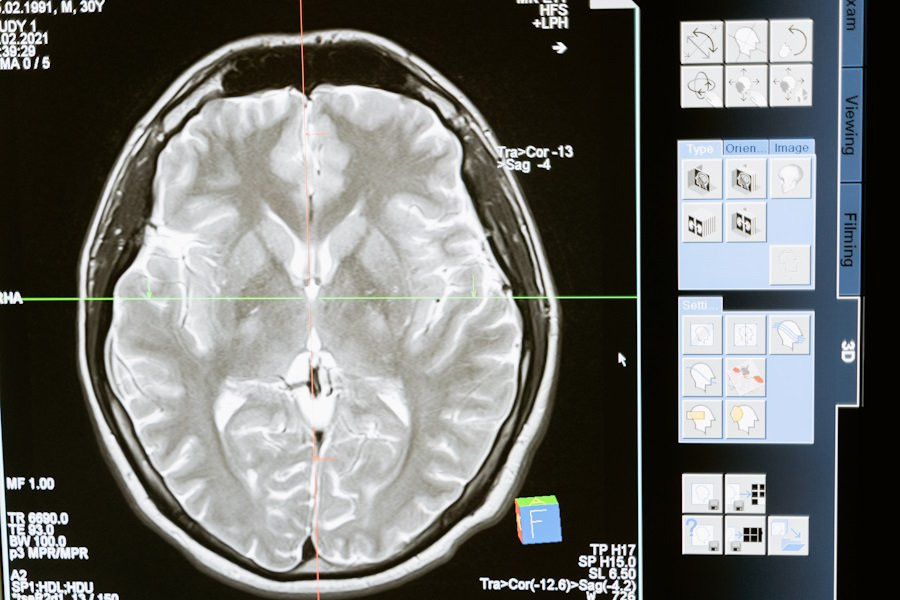

В Санкт-Петербургском политехническом университете создана компьютерная программа SpineTool. Эта программа предназначена для автоматического анализа изображений мозга и определения формы отростков нейронов, которые называются дендритными шипиками, пишут "Известия".

SpineTool шаг за шагом анализирует эти изображения и строит трехмерную модель дендритных шипиков. При этом каждый шипик уникален, и нет двух одинаковых по форме. Раньше ученые использовали числовые параметры, такие как длина, ширина и объем, чтобы описать шипики. Но это давало только абстрактное представление об их структуре. Российские специалисты впервые выделили отдельные сегменты в изображении шипиков и на основе этих сегментов построили столбчатую диаграмму, которая называется гистограммой.